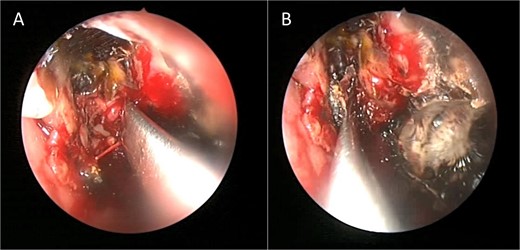

Intra-operative endoscopic view showing (A) polyps in the left osteomeatal complex with (B and C) fungal mud and mucin.

Intra-operative endoscopic view showing invasive fungal granuloma in the right maxillary sinus.